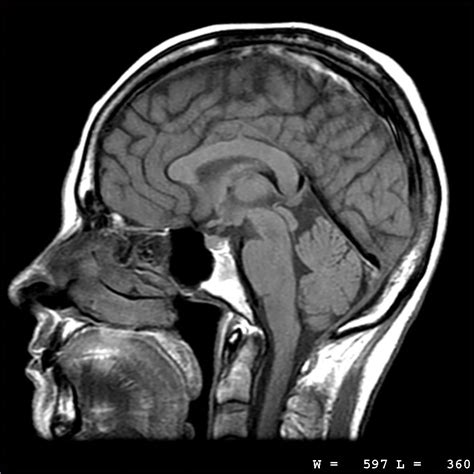

So, you might be asking, “ How does this whole MRI thing even work?” It sounds like science fiction, right? Well, it all boils down to the magnetic fields and radio waves . Your body is mostly made up of water, and water molecules have tiny parts called protons. These protons are like little spinning tops, and when you’re not in a magnetic field, they’re all spinning in random directions. But here’s where the magic happens: when you lie inside the MRI scanner , which is basically a giant, super-strong magnet, all those protons line up, kind of like a compass needle pointing north. Pretty neat, huh? The MRI machine then sends out a burst of radio waves . These radio waves knock the protons out of alignment, but only for a second. As they snap back into place, they release energy, and this energy is picked up by special receivers in the MRI machine. Different tissues in your body – like fat, water, or muscle – release this energy at different rates and strengths. The computer then translates these signals into detailed cross-sectional images of your body. Think of it like a super-sophisticated sound recording; the echoes tell the computer what’s there and where it is. The stronger the magnetic field, the more detailed the images can be. That’s why MRI machines are housed in special rooms to shield them from outside magnetic interference, and why you might hear a lot of loud banging and whirring noises – that’s just the machine doing its job, rapidly turning the magnetic field on and off to create those images. It’s a complex symphony of physics that gives us an incredible window into your body.

Doctors recommend MRI scans for a whole host of reasons, guys. It’s a go-to diagnostic tool when they need to get a really clear look at soft tissues, which are often hard to see on other types of scans. For instance, if you’ve injured your knee playing sports and suspect a torn ligament, an MRI can show the extent of the damage with amazing clarity. Think about problems with your brain and spinal cord MRI is fantastic for detecting things like multiple sclerosis (MS), tumors, strokes, or herniated discs. It’s also invaluable for examining organs like the liver, heart, and prostate, helping to identify abnormalities or diseases. For cancer detection and staging, MRI can provide detailed information about the size, location, and spread of a tumor, helping oncologists plan the best course of treatment. Even conditions affecting your joints, muscles, and tendons, such as arthritis, tendonitis, or tears, are clearly visualized. Sometimes, a doctor might use MRI to follow up on an earlier diagnosis or to check the effectiveness of treatment. The non-invasive nature (no surgery required!) and the high level of detail make it a crucial part of modern medicine. So, if your doctor suggests an MRI , it’s because they need that super-detailed picture to figure out what’s going on and how best to help you get better. It’s a powerful tool in their arsenal for keeping us healthy.